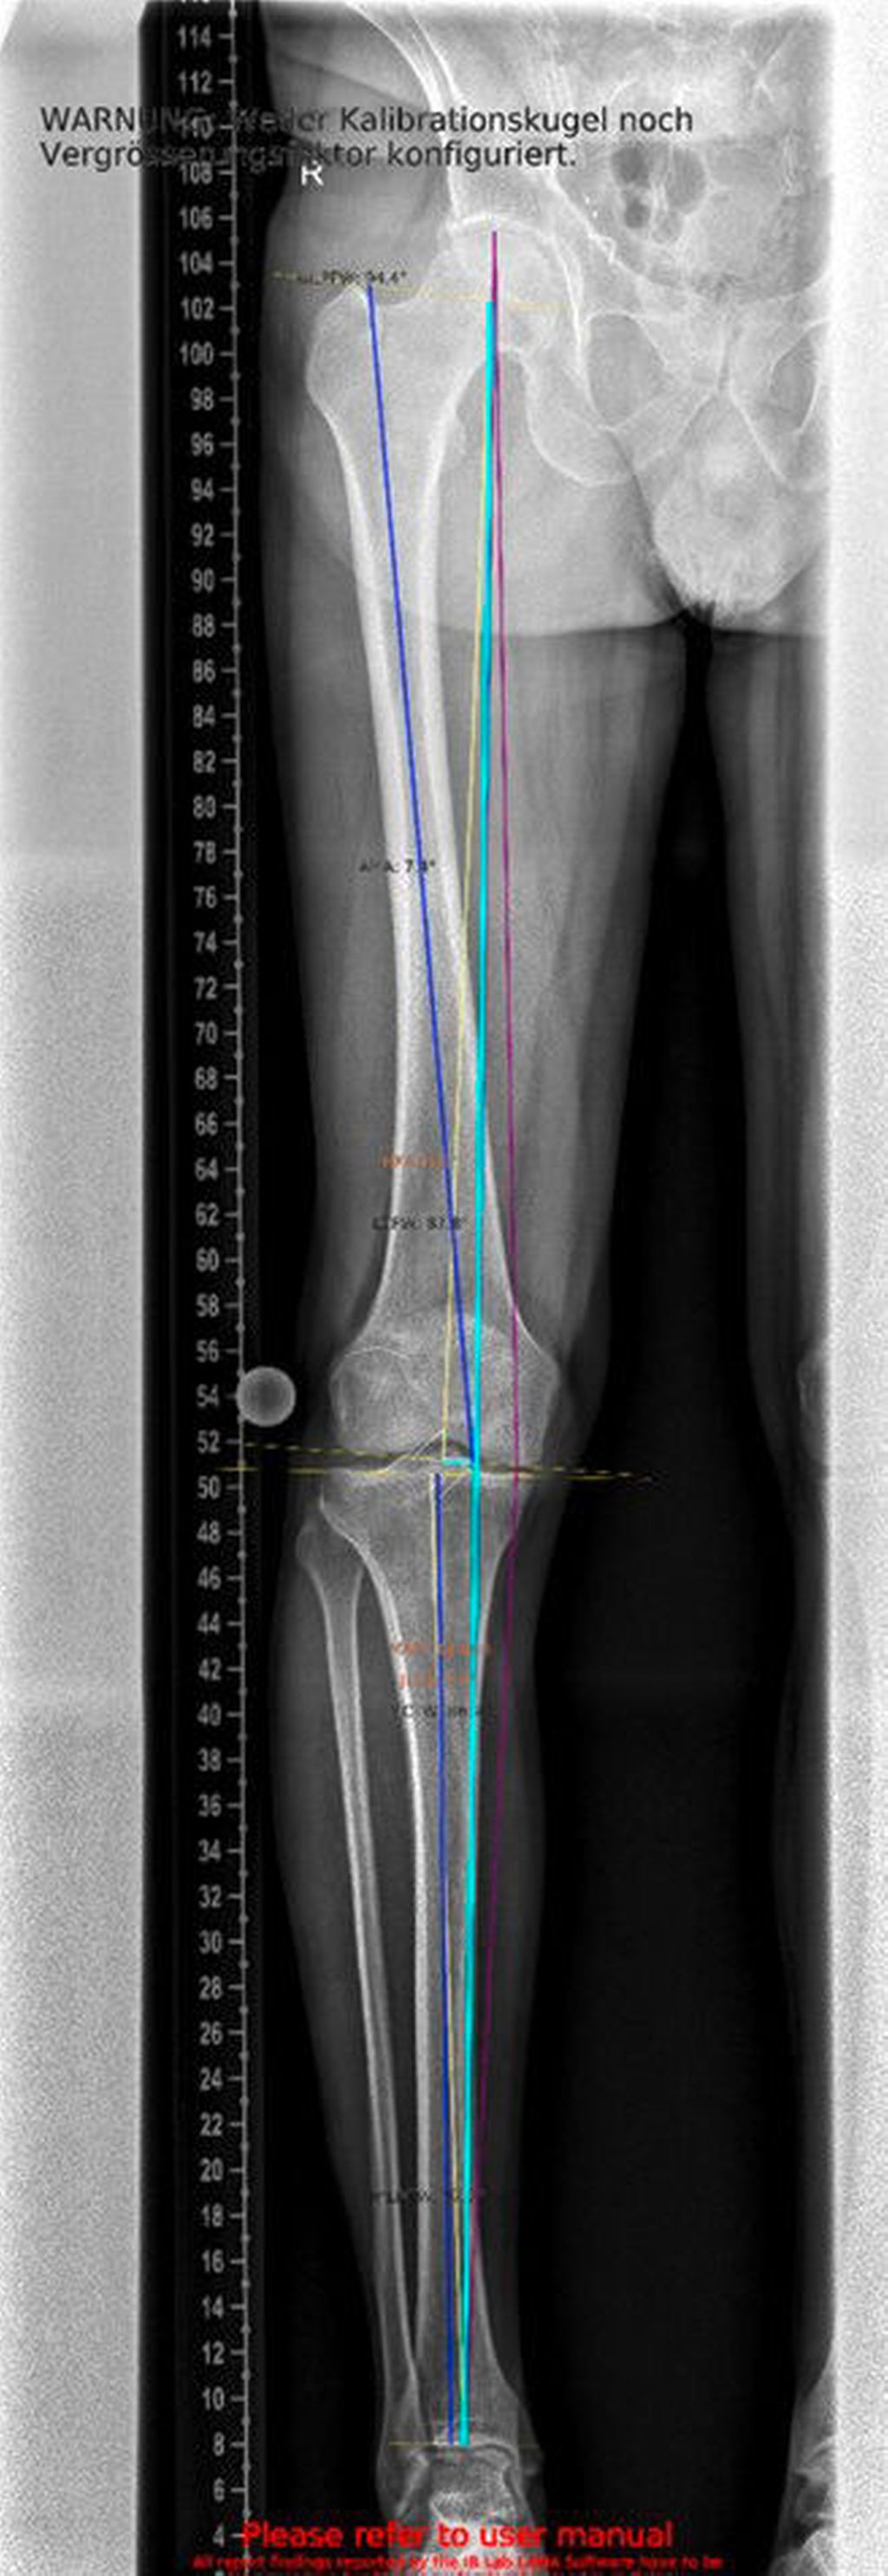

Ein weiterer kritischer Aspekt ist das Risiko für eine postarthroskopische Osteonekrose. Hinsichtlich der Pathogenese werden unterschiedliche Ursachen diskutiert: Zum einen gelten Meniskusläsionen als möglicher Hauptfaktor, zum anderen werden intraoperative Traumata, ein erhöhter intraartikulärer Druckanstieg während der Arthroskopie sowie veränderte Lastübertragungen nach partiellen Meniskusresektionen als ursächlich in Betracht gezogen.17 Nach partiellen Meniskusresektionen kann es zu einem signifikanten Anstieg subchondraler Druckspitzen kommen. Diese mechanische Überlastung fördert die Entstehung von Mikrofrakturen sowie subchondralen Perfusionsstörungen, die in der Folge in eine Osteonekrose übergehen können. Kobayashi et al. berichteten, dass bei 25% der Patient:innen nach partieller Meniskektomie eine juxtaartikuläre Osteonekrose auftrat, nach totaler Meniskektomie sogar bei 50%. Die Lokalisation der Nekrosen war variabel: In 16 von 32 Fällen manifestierten sie sich sowohl am tibialen als auch am femoralen Kondylus, in zehn Fällen isoliert am Tibiaplateau und in sechs Fällen ausschließlich am Femurkondylus. Nach medialer Teilmeniskektomie zeigte sich eine Prädisposition zur Manifestation im medialen femoralen Anteil, wohingegen nach lateraler Teilmeniskektomie überwiegend der laterale tibiale Anteil betroffen war.18 In der klinischen Praxis bedeutet dies, dass präoperativ eine alleinige MRT-Untersuchung des Meniskus nicht ausreicht. Vor allem bei klinischem Verdacht auf eine Achsenabweichung sollte eine Ganzbein-Standaufnahme zusätzlich durchgeführt werden. Nur so lässt sich die mechanische Beinachse zuverlässig beurteilen und in die Therapieplanung einbeziehen.

Ein 62-jähriger Patient stellte sich im März 2025 mit belastungsabhängigen Knieschmerzen rechts vor. Im MRT zeigte sich eine Läsion des medialen Meniskus, sodass in Zusammenschau mit dem positiven Meniskuszeichen in der klinischen Untersuchung eine partielle Meniskektomie durchgeführt wurde. Die postoperative Phase verlief zunächst unauffällig. Der Patient berichtete über ein beschwerdefreies Intervall von rund sieben Wochen. Anschließend entwickelten sich jedoch erneut zunehmende Schmerzen im rechten Kniegelenk, die eine erneute Vorstellung in der Spezialambulanz erforderlich machten. Er berichtete vor allem über belastungsabhängige Schmerzen im Bereich des medialen Kniegelenks. Daraufhin wurde ein Ganzbeinröntgen zur Beurteilung der Beinachse durchgeführt, hier zeigte sich eine varische Beinachse mit 5 Grad Varus (Abb.1). In der ergänzend durchgeführten MRT-Untersuchung konnte medialseitig eine ausgeprägte Nekrosezone am medialen Femurkondyl nachgewiesen werden (Abb.2). Schlussendlich wurde aufgrund dieses Befundes die Indikation zur Implantation einer medialen Hemischlittenprothese rechts gestellt, die schließlich im August 2025 komplikationslos durchgeführt wurde (Abb.3+4).